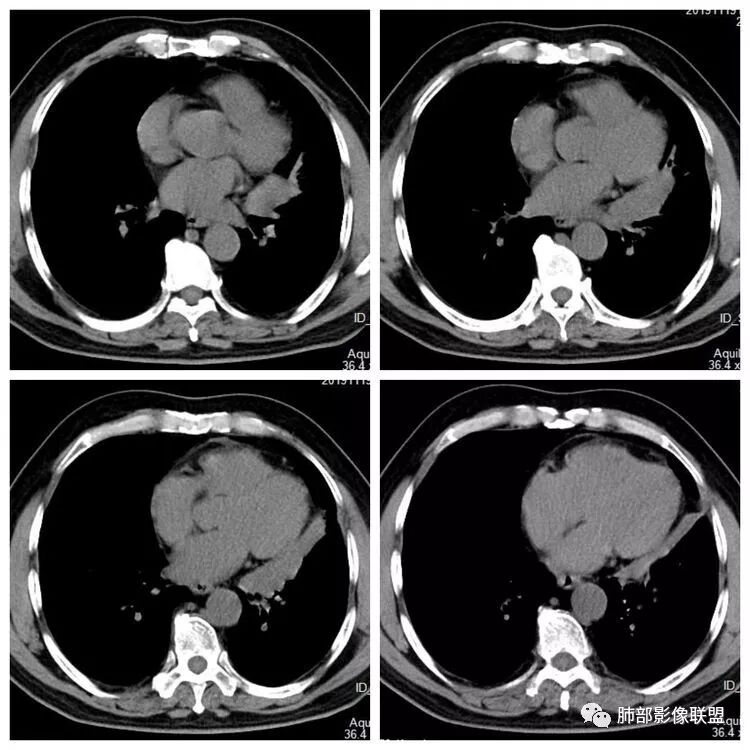

平扫 动脉期 静脉期  40HU、48HU、57HU

患者老年男性,“左肺占位”收入住院。查CEA轻度升高。胸部CT:左肺肺门占位并左肺下叶阻塞性,远端肺组织膨胀不全,增强可见轻度强化,内似见低密度灶。双肺多发类圆形结节,以左肺上叶尖后段为大,内可见部分钙化,边缘光滑、清楚。综合考虑恶性病变,鳞癌并转移可能大,鉴别腺癌、结核。

4.增强扫描左肺门区块影轻度强化,强化程度轻于舌段周围不张肺组织。

左肺上叶孤立小结节影未见异常强化。

6.分析:男性患者,左肺门区块状影,支气管阻塞,强化不显著,未见淋巴结肿大,更多见于肺鳞癌。难以解释的是下肺病灶的生长方式。

沿肺门或是叶裂缺损孤立发生且蔓延,转移性腺癌似乎可以解释,但占据较大支气管腔就属罕见了。

本例很难首先怀疑转移灶。

病例结果:2年前直肠癌根治术后改变,中分化腺癌,支气管镜检:转移性腺癌。